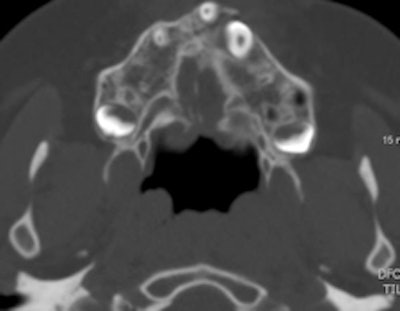

For alveolar bone graft planning, use CT with multiplanar reconstructions (MPR) and surface volumetric (3D), the authors recommended. For planar measurements, axial and coronal CT scans and volumetric measurements before bone grafting give a more accurate picture and help with surgical planning.

"Three-dimensional CT data is especially helpful in evaluating patients with severe craniofacial asymmetry, because they do not suffer from the magnification and distortion-related problems inherent in 2D projections," the authors wrote.

An 8-year-old girl with unilateral cleft lip and palate. Planar measurement (axial) and volumetric measurement before the alveolar bone graft (volume: 1.43 cc3).In the four- to six-month follow-up after alveolar bone grafting, the outcome checklist comprises assessment of bone bridge development (osseointegration), measurement of the bone volume of the graft on 3D CT, checking for the presence of oronasal fistula, and evaluation of facial symmetry. Reabsorption of the bone graft occurs mainly during the first postoperative three months and is closely related to long-term outcome, while normal resorption after one year can be up to 30% to 50% of the original graft volume.